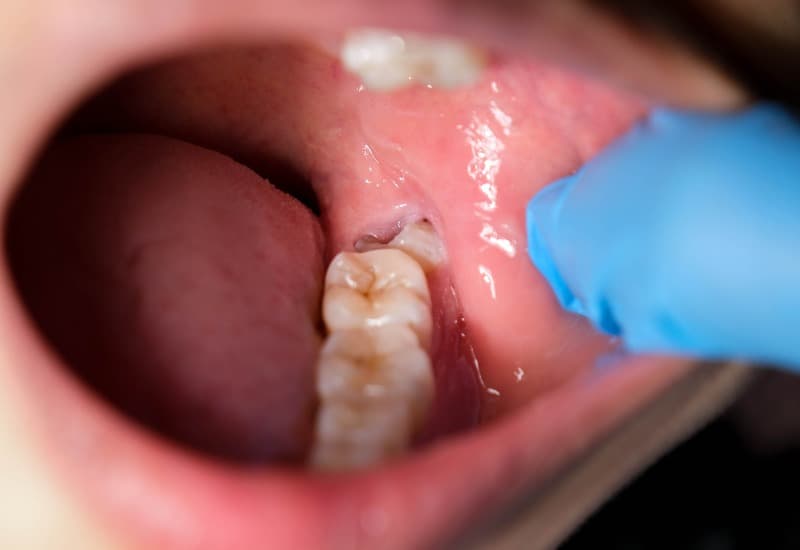

– Răng khôn mọc lệch hoặc răng khôn mọc ngầm: Răng khôn mọc lệch ra ngoài hoặc vào trong, răng khôn mọc ngầm dưới nướu, gây áp lực lên các răng liền kề, dẫn đến đau nhức, và nhiều vấn đề khác trong quá trình sinh hoạt hàng ngày.

Răng khôn mọc ngầm dưới nướu, gây áp lực lên các răng liền kề.